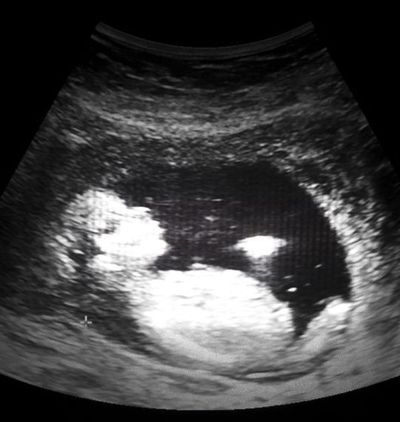

/ 6Problemy

Czy historia Irmy jest precedensowa? Zdaniem wielu specjalistów ten przypadek dobrze obrazuje, jak wygląda opieka zdrowotna w Meksyku. Setki kobiet wciąż umierają w czasie lub krótko po porodzie. Ciągle istnieje też problem dotyczący dyskryminacji rdzennych mieszkańców Meksyku.

- To zdjęcie obrazuje istnienie większego problemu. Kobiety nie otrzymują odpowiedniej opieki medycznej. Czasami nie mogą liczyć nawet na ludzkie traktowanie - mówi Mayra Morales, reprezentantka Network for Sexual and Reproductive Rights. Śmiertelność noworodków w Meksyku wciąż jest bardzo duża, umiera ok. 50 na 100 tysięcy nowonarodzonych dzieci. Dla porównania, w Kazachstanie ta wartość wynosi 16 na 100 tys.